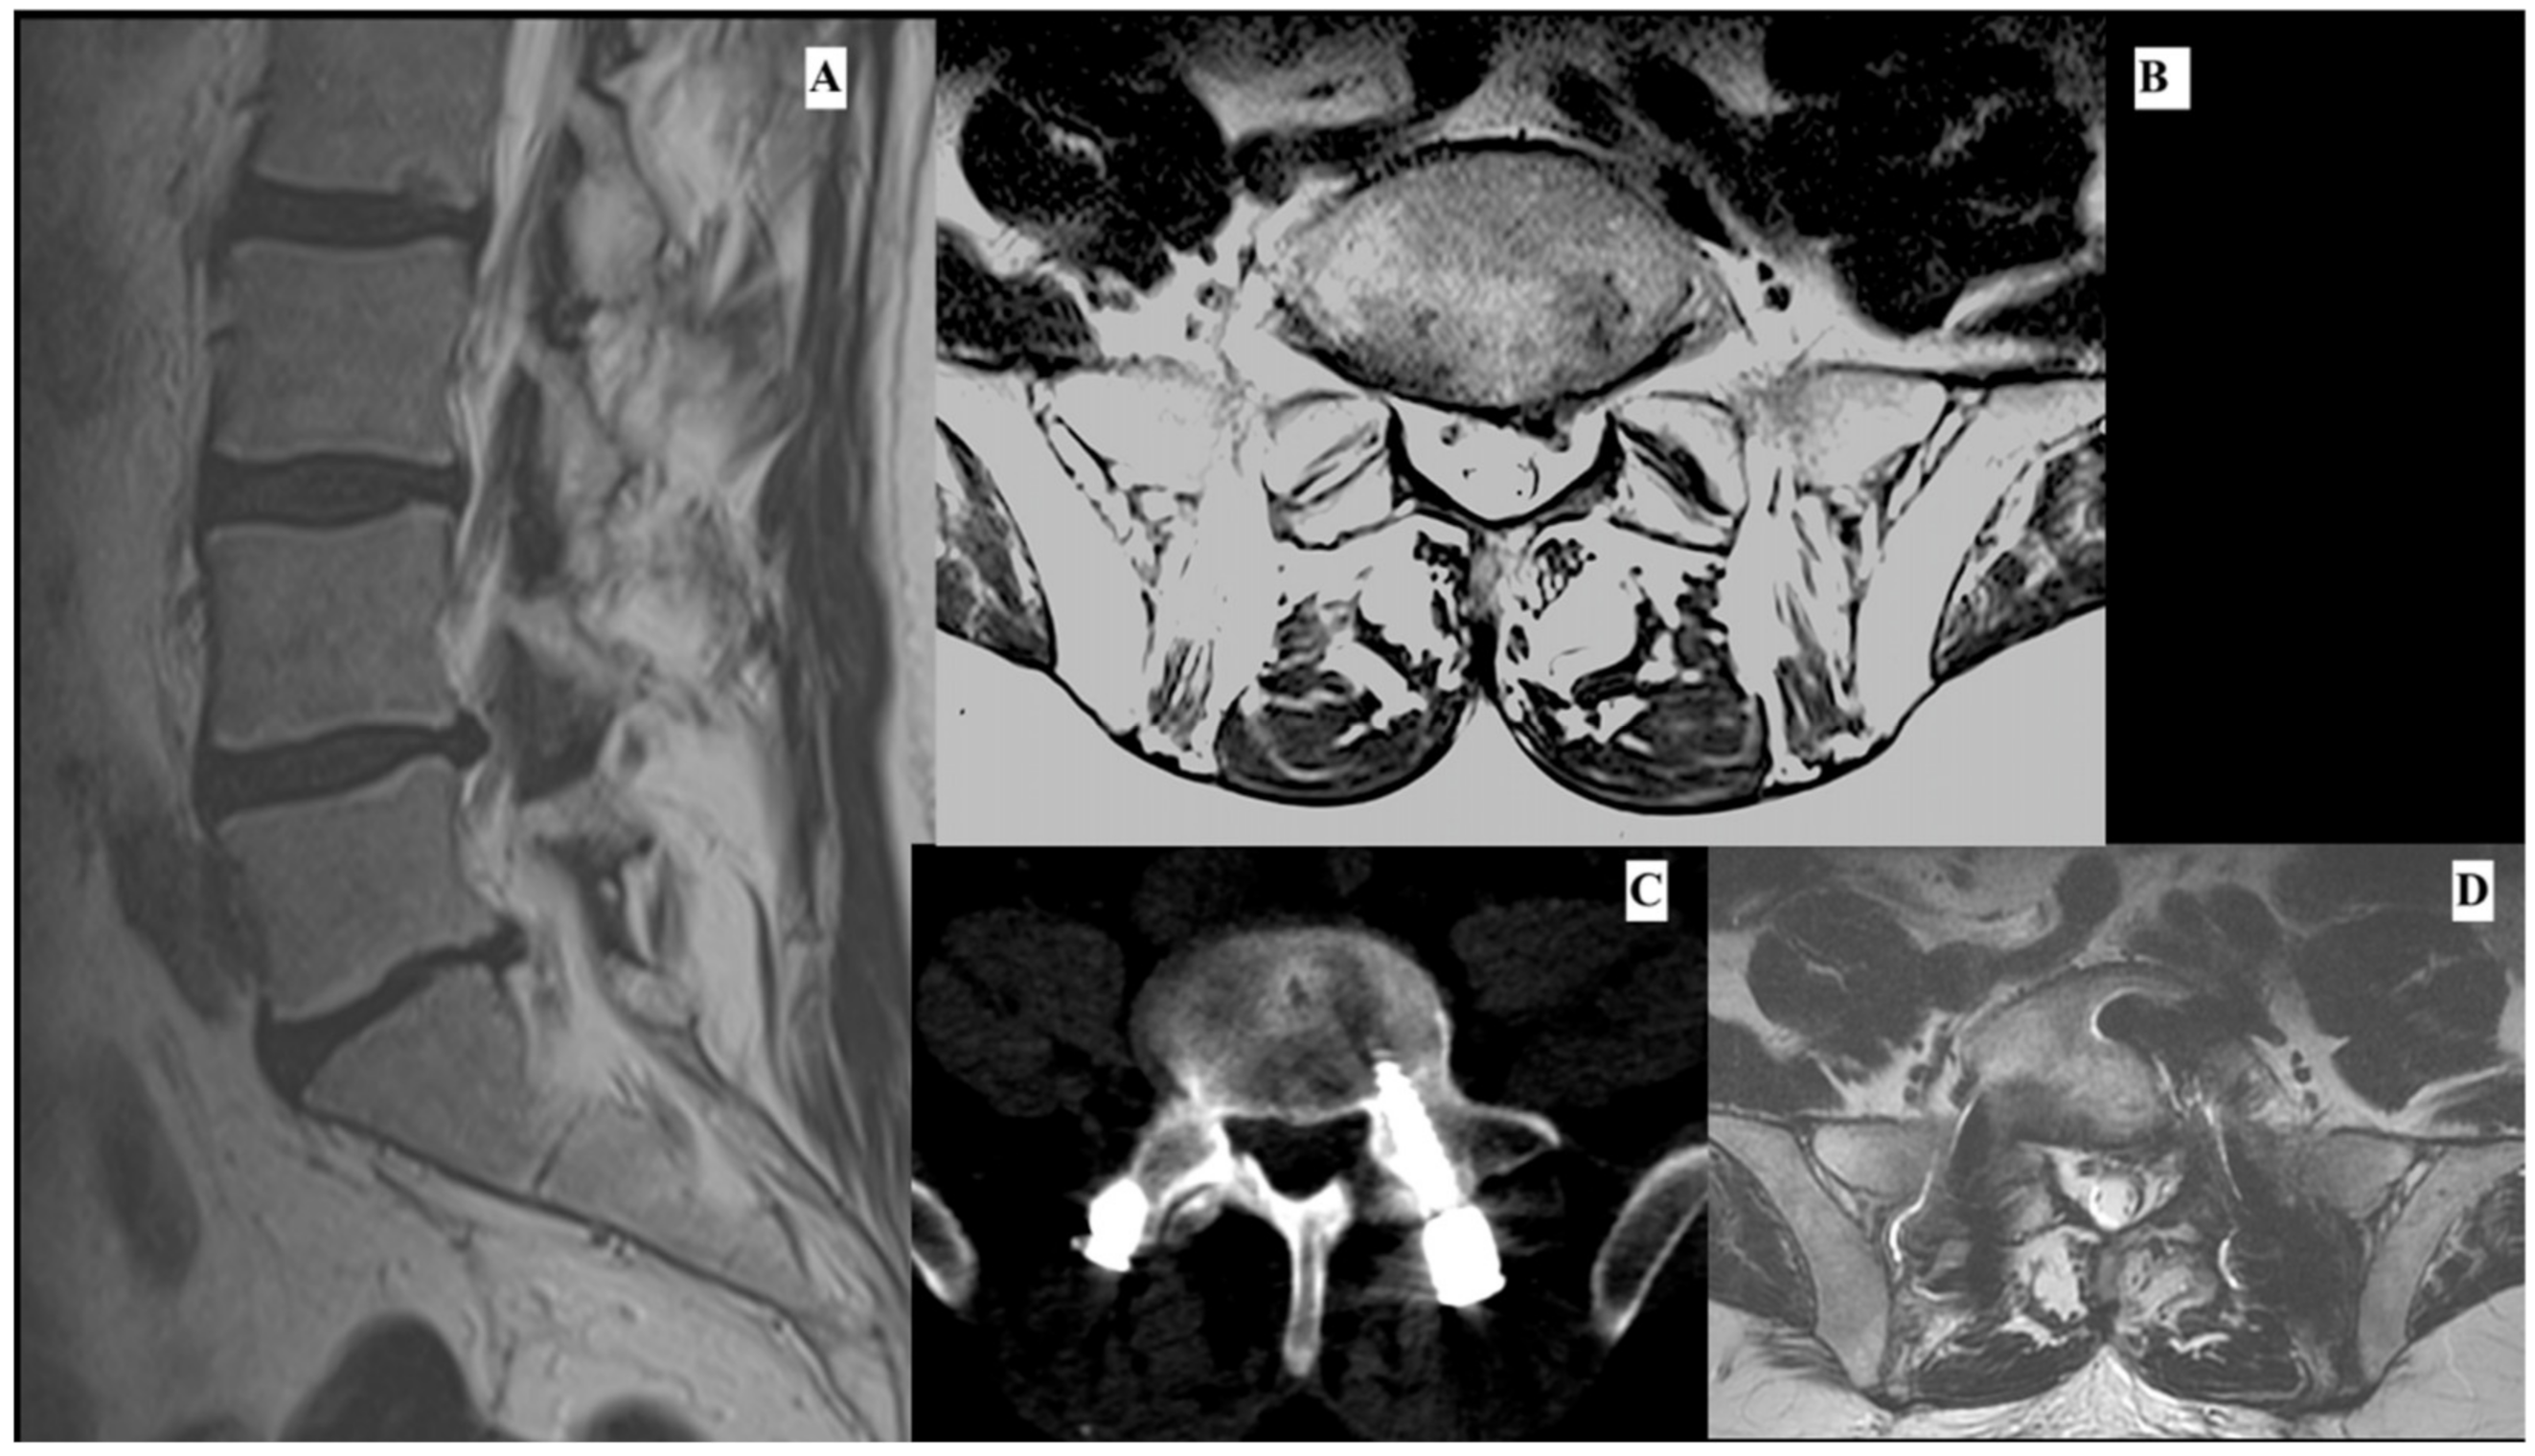

A 61-year-old man, with clinical history of colon cancer 5 years before, was admitted to our department after complaining about low back pain with irradiation along the left leg and dysesthesia of L5 dermatome lasting for 6 months. Magnetic resonance imaging (MRI) examination revealed the presence of L5-S1 lumbar disk herniation with instability (retrolisthesis, Modic type I. Figure 2A,B). The patient was treated with anterior and posterior arthrodesis of L5-S1 using transforaminal lumbar interbody fusion using the minimally invasive spine surgery (MIS-TLIF) technique and L5-S1 discectomy (Figure 2C,D). The procedure and postoperative course were uneventful and prompt discharge occurred. Ten days after the discharge, the patient reported a new onset of paresthesia and dysesthesia on the back of the left foot along with the territory of the L5 nerve.

Figure 2.

This shows a sagittal (A) and axial (B) imaging of preoperative lumbar MRI. It is possible to see a paramedian-intraforminal left lumbar disk hernia. The image shows an axial slice of postoperative lumbar TC (C). It is possible to observe the correct positioning of the screw. Image (D) shows an axial slice of lumbar MRI, which was performed 1 month after the first surgery due to the continuous intractable pain. It is possible to observe at level L5-S1 a paramedian left lumbar disk hernia (D).

The initial symptoms were change in progressive pain, particularly low-back pain with irradiation of the left leg with night exacerbation. The patient started treatment with NSAID, pregabalin, and myorelaxant, with low pain control. Due to the relentless and worsening of the pain, a new lumbar MRI was performed, showing the presence of recurrent L5-S1 paramedian disk herniation (Figure 2C,D) and a new surgical intervention was performed.